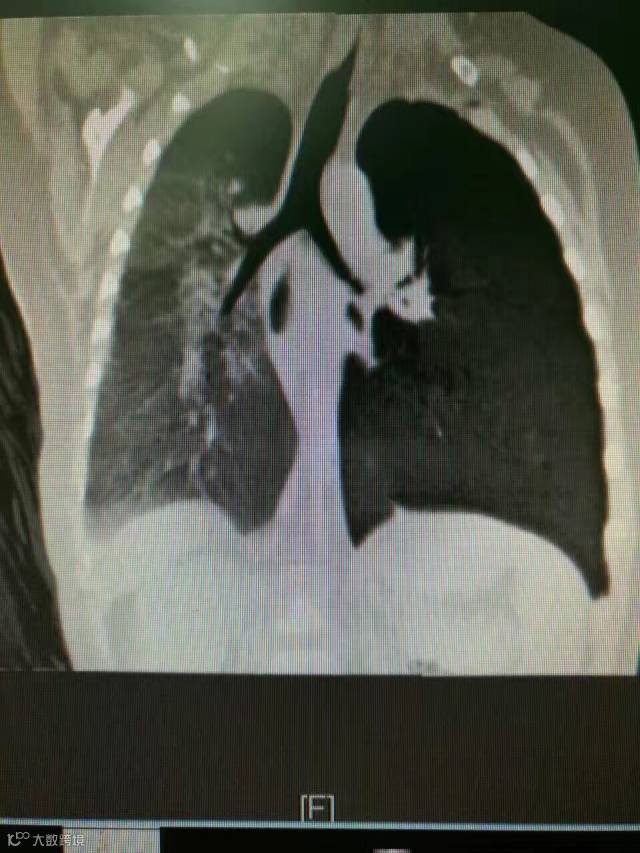

近日,广州市一个9个月的宝宝反复肺炎3个月,在诊断中“CT提示支气管异物,纤维支气管镜下见异物位于左下叶基底段,尝试夹取异物未成功。”最终医生用支气管硬镜取出2mm大小的蓝色塑料珠。